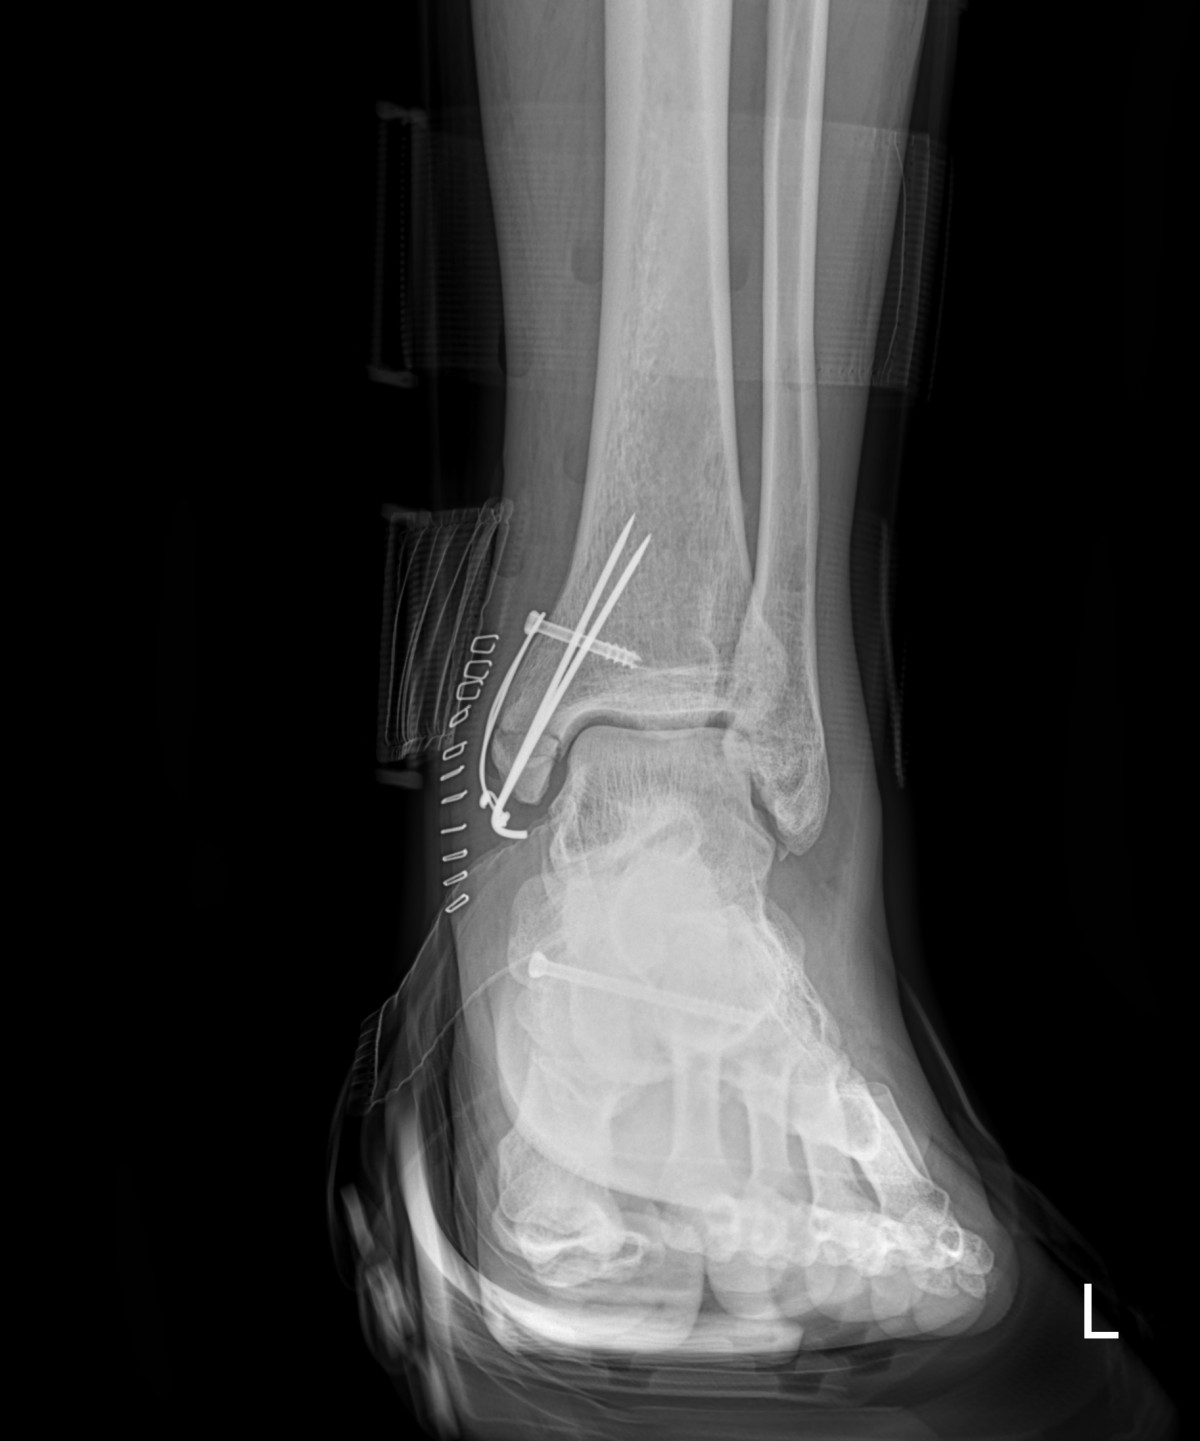

이재상원장님 발목 골절 수술 유현O 환자

dae765e4d9ac96aee867c9d6292d8784_1758002544_736.jpg